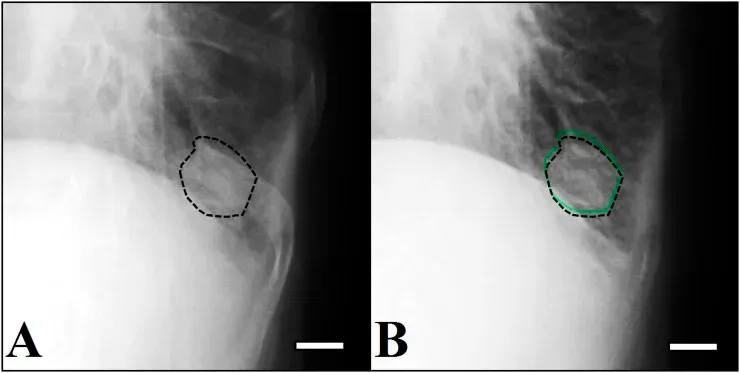

Antes da aplicação do deep learning na área da saúde, os investigadores tentaram usar a correspondência de modelos para otimizar o fluxo de trabalho e auxiliar na identificação de anomalias. Um bom exemplo dessa técnica está relacionado à deteção de tumores ou nódulos pulmonares.

Neste método, os investigadores criam modelos de referência que representam a forma e a intensidade típicas de um tumor. Em seguida, o sistema desliza esses modelos pelas imagens dos pacientes, medindo a semelhança em cada coordenada.